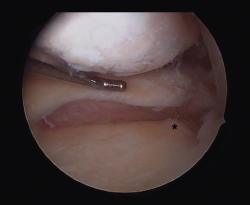

Other diagnostic tests are radiographs under stress varus conditions. We can find indirect radiological signs such as Segond fracture and the arcuate sign. MRI is of great help. Gelber et al. recently reported that over 80% of a group of world experts in the treatment of posterolateral angle injuries agree on the usefulness of MRI in the diagnosis of these lesions(17). Lastly, arthroscopy can offer additional information in the surgical cases (Figure 2).

Figure 2. Arthroscopic view through the anterolateral port of damage to the meniscus-popliteal ligaments (*) at the level of the popliteal hiatus, leaving the tibia exposed (T). P: tendon of the popliteus muscle. Right knee.